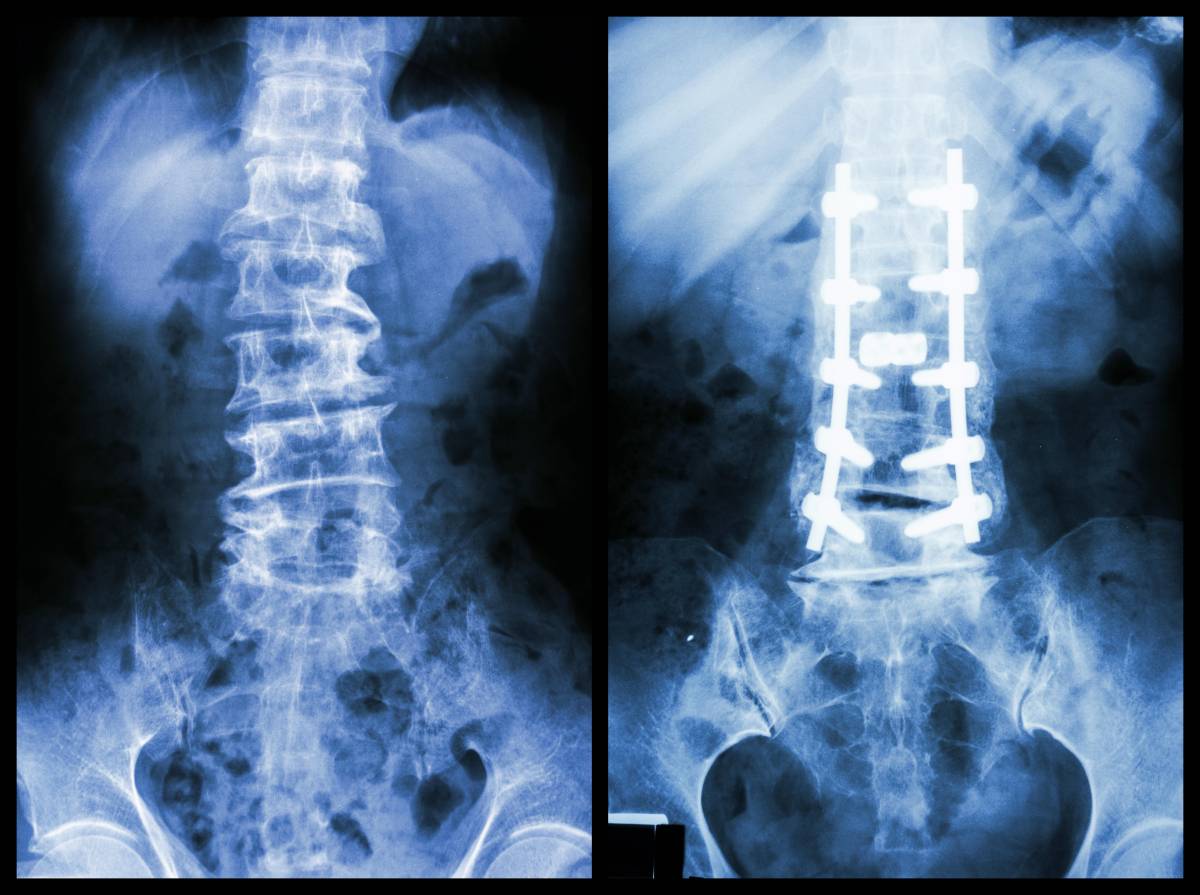

脊柱外科

包括颈椎、胸椎、腰椎、骶骨、尾骨。像大家耳熟能详的腰椎间盘突出症、颈椎病、腰椎管狭窄、腰椎滑脱、腰椎骨折、腰椎结核等,只要是和脊柱相关的,都可以到脊柱外科就诊。除此之外,因为脊髓和神经根也都是从脊柱发出的,所以脊髓和坐骨神经的毛病也归脊柱外科管,比如坐骨神经痛、脊髓损伤等。再有就是脊柱的一些畸形,比如脊柱侧弯、脊柱后凸、强直性脊柱炎的矫形等。总之,只要牵扯到颈椎、胸椎、腰椎,找脊柱外科就对了。